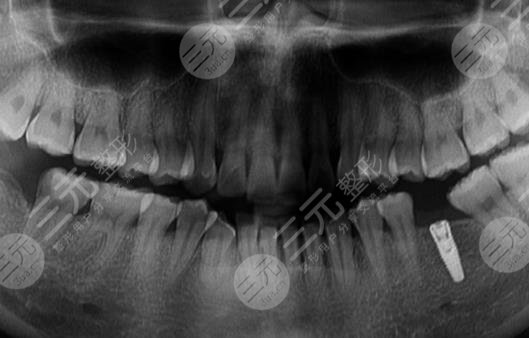

在手术之前,专业的医生对口腔状态进行了一定的了解,然后也对每一颗牙齿的形态和轮廓进行了一定的查看,带领我去做了一系列的医学检查,所有的检查报告都显示现在的口腔状态是能够做缓解,并且也是告诉我牙齿的情况不适合做补牙了,同只能进行牙齿种植了,所以较后我就进行了长达4个月的种植牙缓解。

种植手术的过程中,我心态其实较为的好,因为自己本身就是一个比较乐观的人,而且医生的技术也较为的高端,所以我也较为的相信医生,整个过程花了一个半小时才结束,然后是等了3个月的恢复期,再去医院安装了牙冠,虽然有一点点漫长,但是缓解的果也算是比较好的,较为的令我满意,看上去极其的美观。